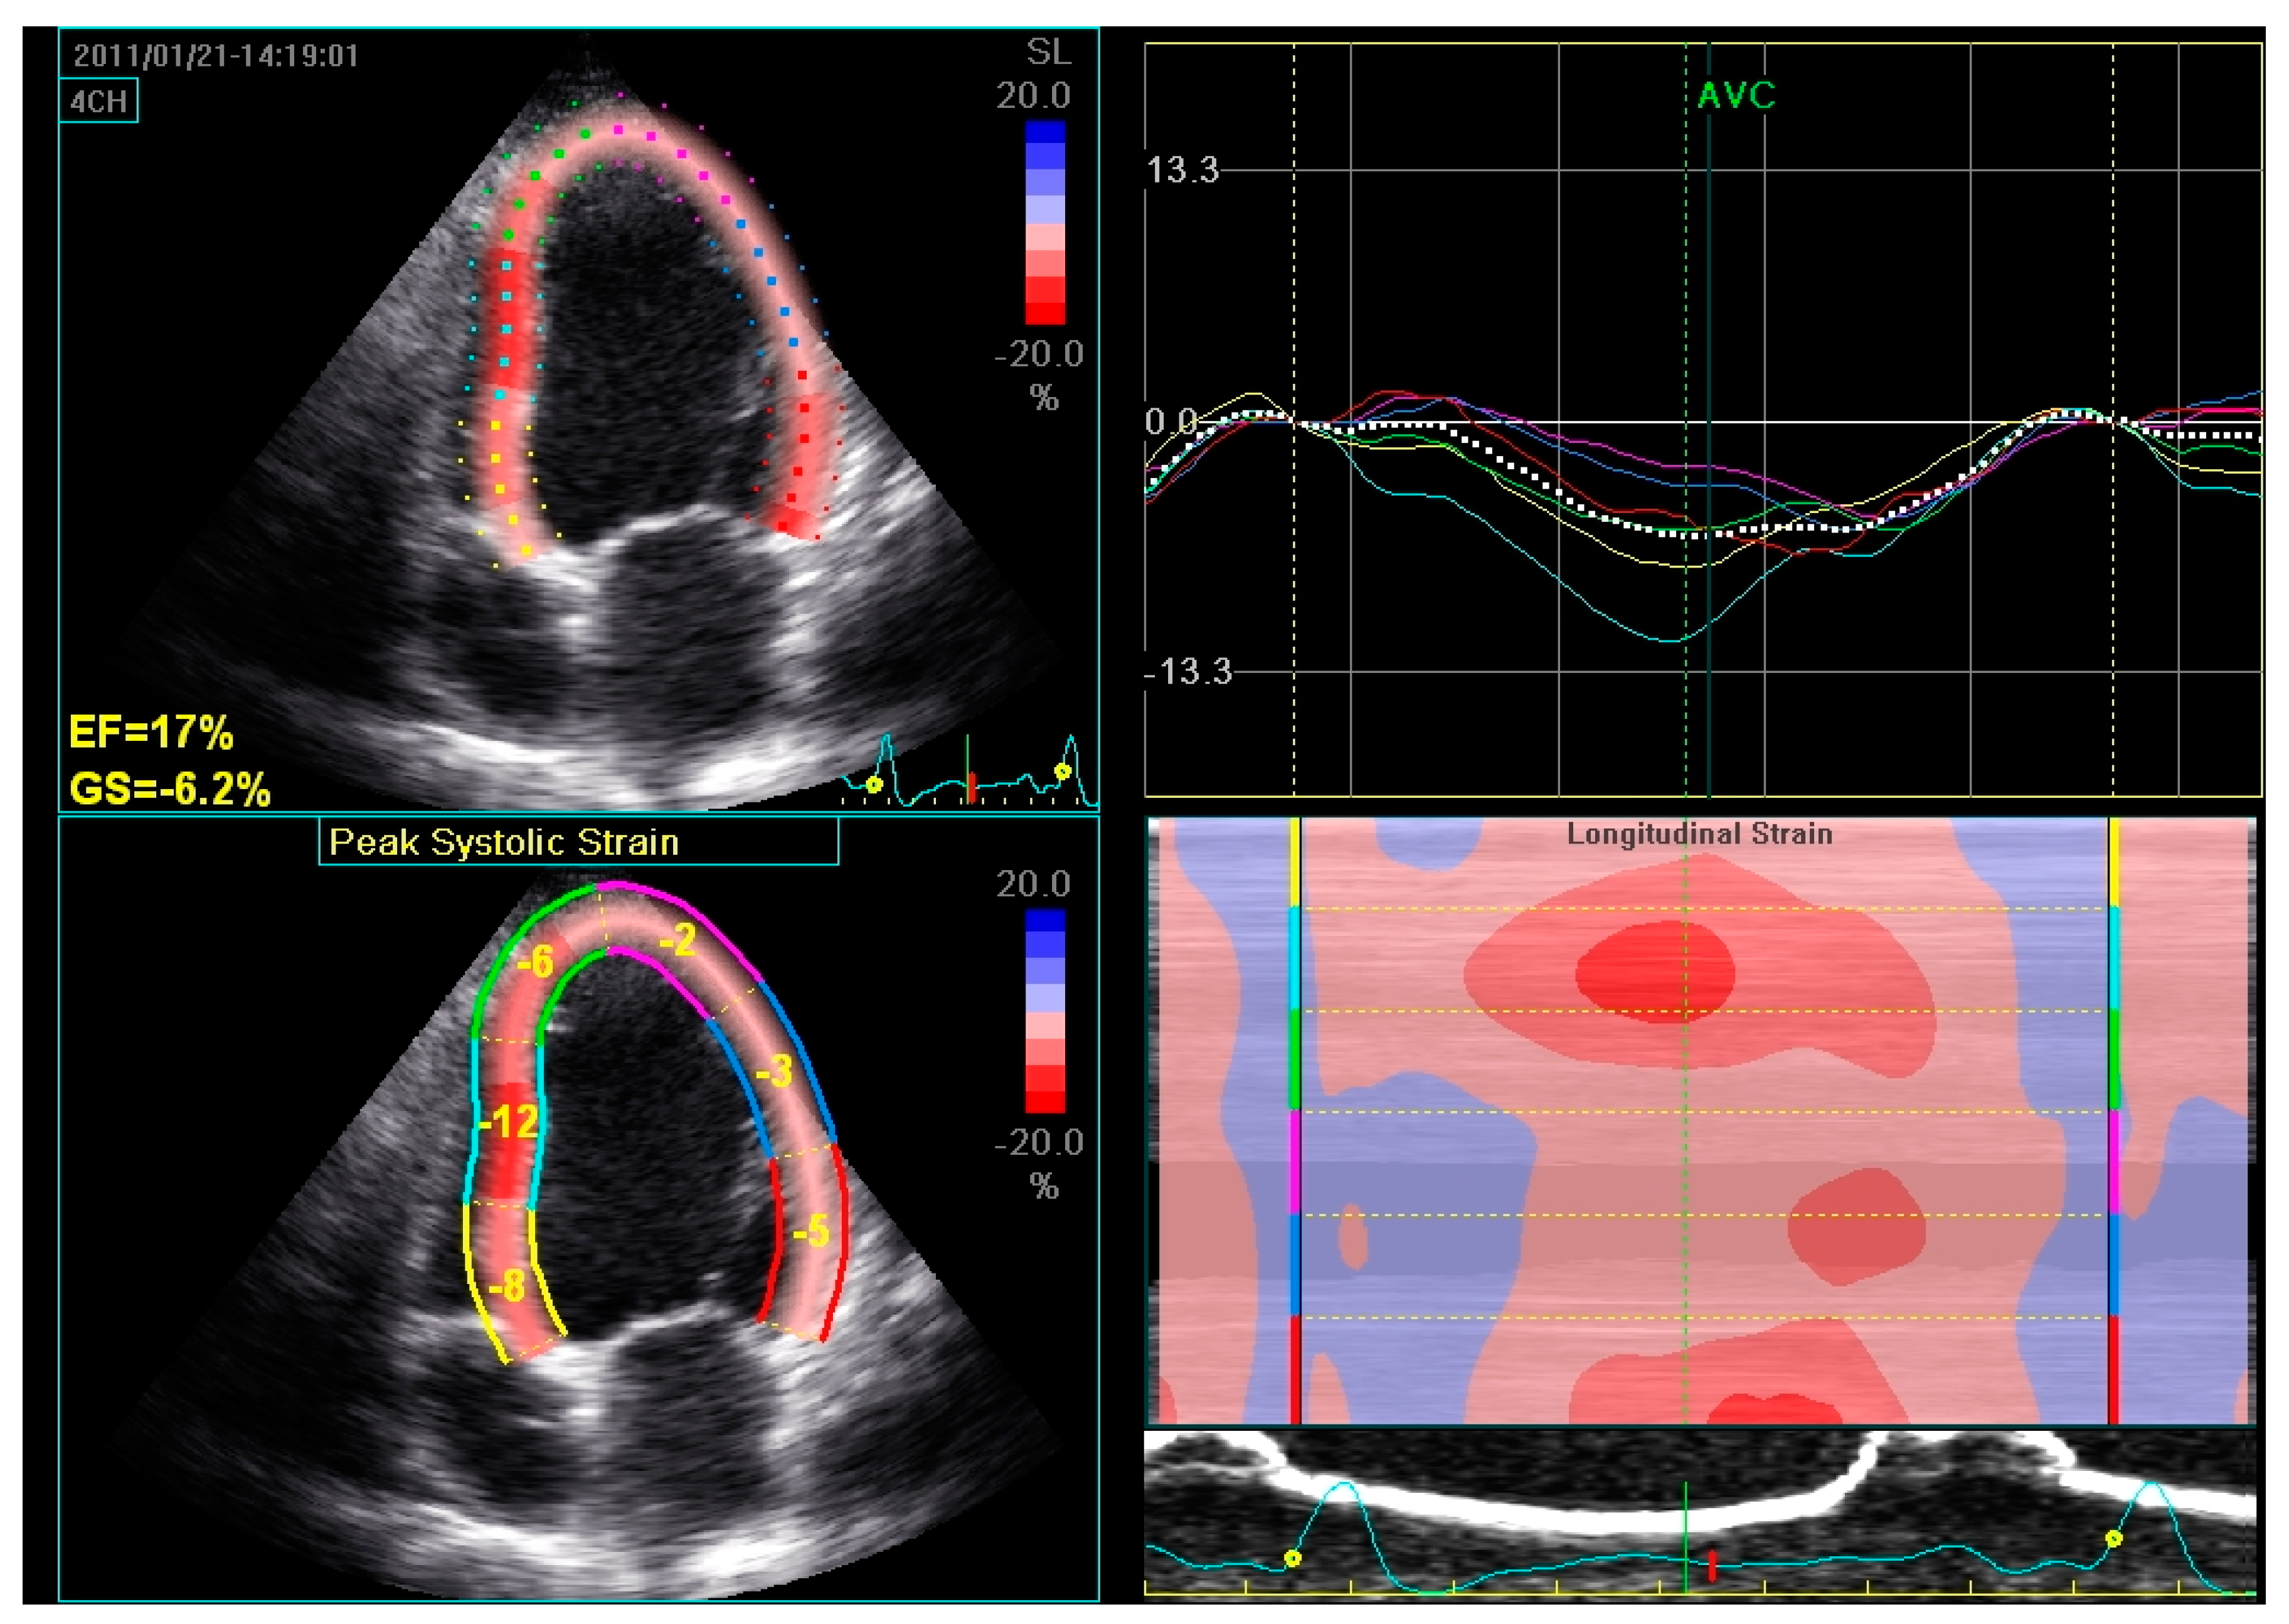

2.1. Assessment of LV Function and Dyssynchrony

- Valzania, C.; Gadler, F.; Boriani, G.; Eriksson, M.J. Changes in global longitudinal strain during rest and exercise in patients treated with cardiac resynchronization therapy. Clin. Physiol. Funct. Imaging 2012, 32, 310–316. [Google Scholar] [CrossRef] [PubMed]